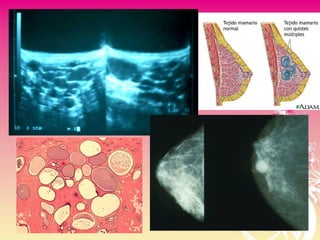

• Los quistes surgen de los lóbulos mamarios y son

• Quistes macroscópicos 7%

• Microscópicos, no palpables 40%

• Frecuentes entre mujeres de 35 a 55 años

El hallazgo de un quiste simple por ecografía descarta el diagnostico de carcinoma.

EnfermedadEnfermedad Quística MacroscópicaQuística Macroscópica

Característica del Tumor:

- Redondeados.

- Bien delimitados.

- Consistencia en relación con la

tensión del líquido. Puede ser blando ó firme

QUISTE DE LA MAMAQUISTE DE LA MAMA